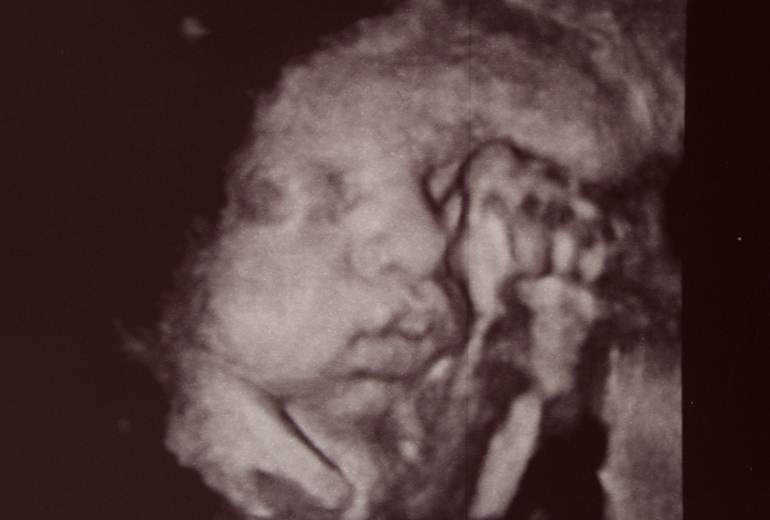

Прикладываю к посту фотографии малышки, сделанные в 20 и в 36 недель. Чтобы сразу становилось понятно, кто тут самый голодающий ;))

На консультации в ЖК, выбор женской консультации/гинекологаПосле "самовыписи" из Снегиревки, я полагала, что для того, чтобы от меня, наконец отстали, будет достаточно заключения заведующего кафедрой трансфузиологии Мечникова, что я гематологически здорова и результатов УЗИ, по которым прибавка моего несчастного, голодающего ребенка составляет 230 грамм в неделю. Что, кстати, даже больше среднестатистических норм. Для иллюстрации, на УЗИ 7 октября, в 33 недели дюймовочка весила 1500-1600 грамм. Через 9 дней, 16 октября, мы нахомячились до 1900-2000 грамм. Вчерашнее УЗИ, 28 октября показало как моя модель отъела изрядные щеки, а вес составил уже 2200-2300 грамм на сроке 36 недель. Кстати, прибавка веса была одинаковой как в условиях больницы, так и на вольных хлебах. Поэтому есть повод задуматься о том, что развитие малышки идет своим чередом, несмотря на пляски теть с иголками и переживания маман)